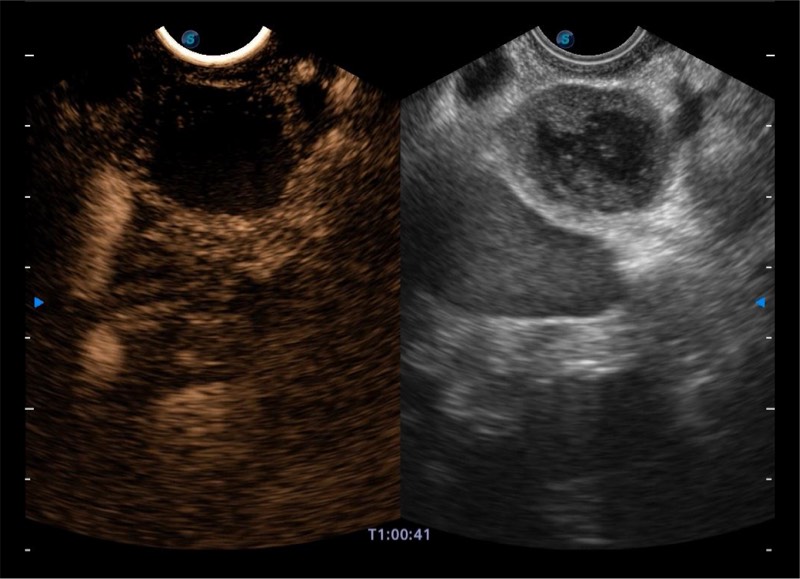

搭载百万级CMOS成像技术

及自主研发凸阵换能器,

可呈现优质的内镜和超声画面

基于二十年的超声技术积累,银河集团官网提供了最新一代的独立超声主机,在提供高质量图像的同时满足多学科使用。具备常见多普勒技术并提供弹性成像、声学造影等高端影像技术。新一代传感器具有更强的抗干扰能力并减少图像伪影。

4-12MHZ宽频输出